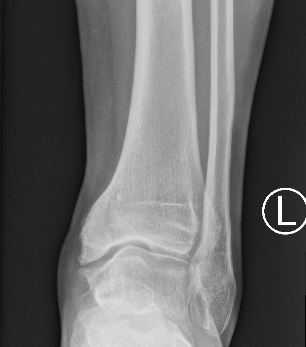

Xray

Ranges from anterior spurring to severe OA

80% of post-traumatic OA is varus

Takakura classification

| 1 | Early sclerosis and formation of osteophytes |

| 2 | Narrowing of the medial joint space |

| 3A | Obliteration of the medial joint space with subcondral bone contact |

| 3B | Obliteration of joint space over roof of talar dome, with subchondral bone contact |

| 4 | Obliteration of joint space with complete tibiotalar contact |

Type 1: Anterior spurs

Type 3A: Obliteration of medial joint space Type 3B: Obliteration medial joint space plus tibio-talar contact with varus

Type 4 complete obliteration